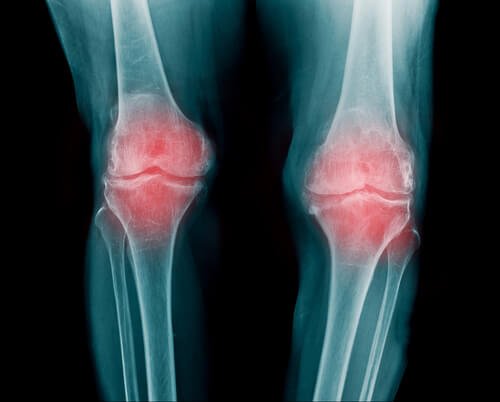

骨の間には関節があります。柔軟で弾力性のある組織、関節軟骨です。軟骨はクッションのような働きをし、骨同士の摩擦を防いでくれます。

- 関節リウマチは関節の炎症です。複数の関節に影響を及ぼすことがあります。一般的に、指、腕、膝の関節が多いでしょう。

- 関節リウマチはカルシウムが関節に蓄積されたときに起こります。関節がうずきだし、軟骨が弱まります。次第に軟骨が減り、痛みが悪化するでしょう。